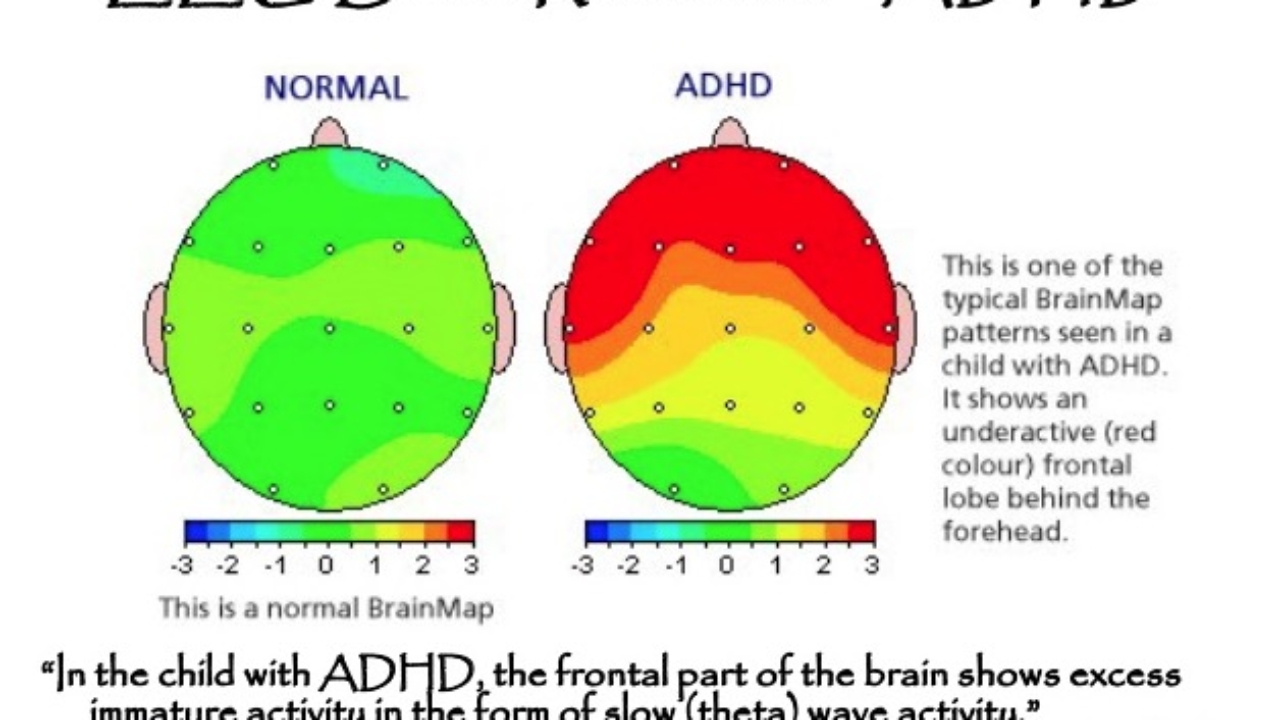

ADHD Brain Vs Normal Brain Functions Differences More

That s why it s vital to stagger the bloom times of your perennials for non stop color Use this list of spring summer and fall blooming perennials for sun and shade to start planning ADHD Brain Vs Normal Brain Differences Explained Unlike summer annuals that bloom consistently over many months, perennials generally have a window of time when their flower flushes appear. By following this guide, you can design a perennial garden that will provide four seasons of interest.

ADHD Brain Differences Stuff4Educators

Adhd Vs Normal Brain Brain Patterns Put Adhd In Focus Australasian